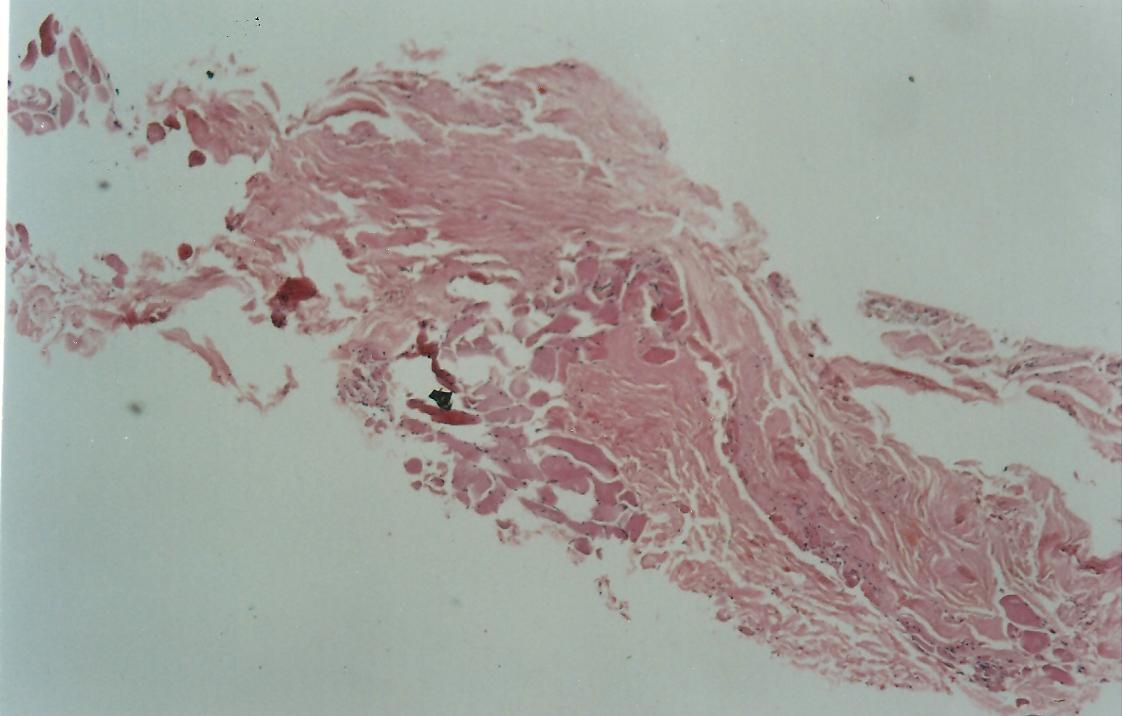

The medial side of the TMF graft is attached to the temporalis muscle after harvesting the graft, the muscle fibres were scraped of the graft. This part of the graft is still rough as compared to the lateral side which is shiny and smooth on microscopic examination. (Figure-1) Before placing the graft it was moistened with saline. In forty one patient technique I was used and in thirty nine patient, technique II was applied.

Figure-1.Fig x40, HE: Shows skeletal muscle on lower left and fibrocollagenous tissue of fascia on upper right